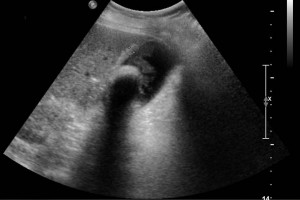

Diplomados en Ultrasonografía